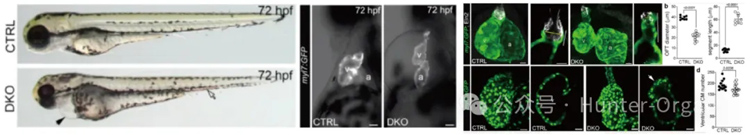

左心发育不良综合征(HLHS) 是严重先天性心脏病,特征为左心系统(心室、瓣膜、主动脉)发育不全,此前认为是多基因协同导致的表型叠加疾病。本研究构建了Rbfox1和Rbfox2双敲除(DKO) 斑马鱼模型,其核心表型与人类HLHS 高度重叠:

①结构层面:心室发育不良、心脏瓣膜异常、主动脉(流出道)狭窄,与人HLHS 的左心系统发育不全特征一致;

②功能层面:心输出量、射血分数显著下降,符合HLHS 患者的心脏泵血功能缺陷;

③外观层面:心包水肿、血液淤积,模拟HLHS 患者的临床并发症表现,为HLHS 研究提供了可靠的在体模型。

心肌特异性过表达Rbfox、mRNA注射野生型人RBFOX2 均可挽救DKO 斑马鱼的缺陷表型,为HLHS 的靶向治疗(如基因治疗、剪接调节剂)提供潜在靶点。